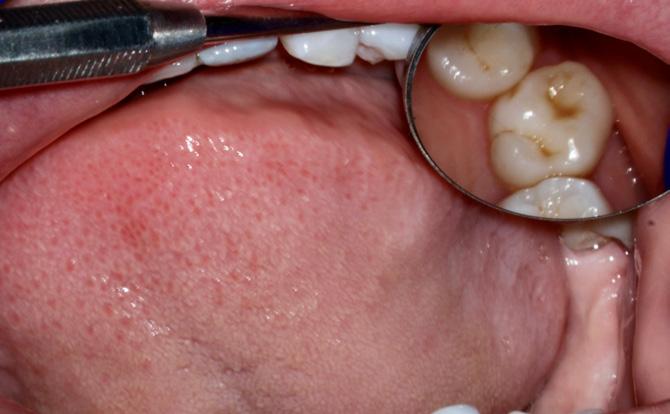

Case 2

Figure 7: Clinical photograph showing left posterior occlusal relationship.

Figure 5: clinical photograph showing teeth in MI (maximum intercuspal) position.

Figure 8: Clinical photograph showing right posterior occlusal relationship.